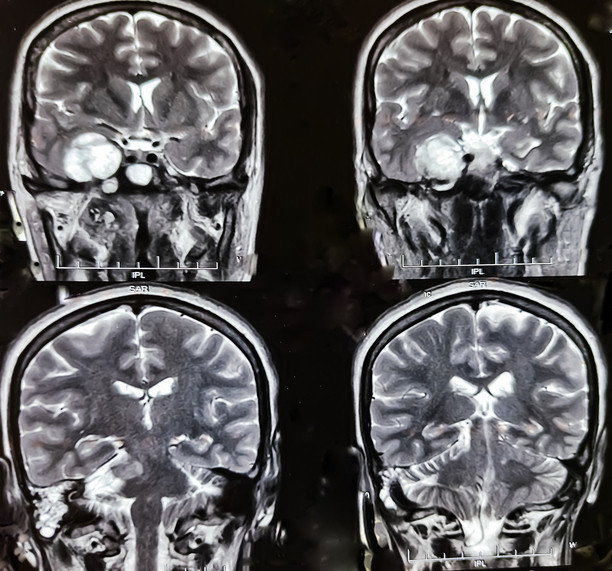

Günümüzde patoloji, sadece mikroskop altında hücre incelemesi yapmanın ötesine geçerek tümörün genetik haritasını çıkarıyor. Yeni nesil dizileme (NGS) gibi moleküler yöntemlerle tümörün DNA'sındaki değişiklikler analiz edilerek; hastalığın seyri öngörülüyor ve doğrudan tümör hücresini hedef alan akıllı ilaçlar seçiliyor.

Bu kapsamda nöronavigasyon teknolojisi cerraha tümöre ulaşması için en kısa ve güvenli rotayı belirleyen dijital bir yol haritası sunarken; fonksiyonel MR ve traktografi yöntemleri beynin konuşma, hareket ve görme gibi hayati merkezlerini haritalandırarak bu kritik bölgelerin korunmasına yardımcı oluyor.

Öte yandan, cerrahi müdahalenin mümkün olmadığı veya şüpheli görülen lezyonlarda devreye giren stereotaktik biyopsi ise yüzde 95 gibi yüksek bir doğruluk oranıyla güvenilir tanı konulmasına olanak sağlıyor.